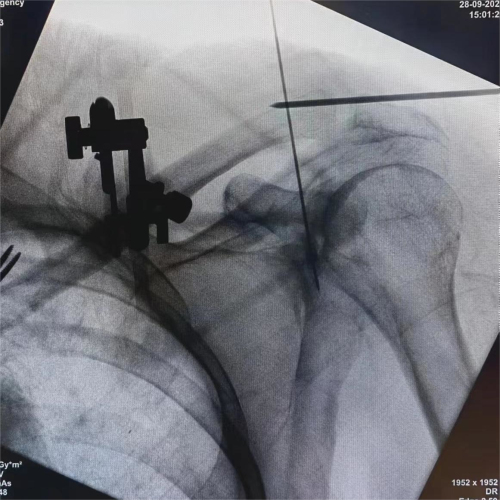

(应用机器人设计钉道)

患者因交通事故致伤导致左肩关节盂骨折及左肩锁关节脱位和右尺桡骨骨折,骨折移位明显,疼痛剧烈,具备手术指征。但患者为75岁高龄,基础疾病多,担心患者无法耐受过大的手术创伤。经术前讨论,创伤外科中心张立峰教授团队决定为患者应用骨科手术机器人辅助经皮内固定治疗肩关节盂骨折的手术方案。术中,通过机器人进行采集数据、并规划手术等人工智能操作,仅用1cm切口即成功完成手术。